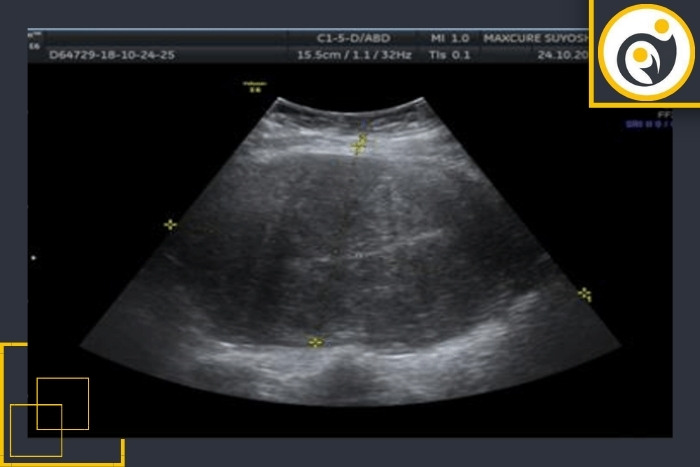

علت بزرگی رحم در سونوگرافی

رحم اندامی عضلانی است که اندازه آن در طول زندگی زن تغییر میکند. در سونوگرافی اندازه رحم بر اساس سن وضعیت هورمونی تعداد بارداری و شرایط جسمانی ارزیابی میشود. زمانی که اندازه رحم بیشتر از محدوده طبیعی باشد اصطلاح بزرگی رحم مطرح میشود. این وضعیت میتواند دلایل مختلفی داشته باشد و همیشه به معنای وجود بیماری نیست. در ادامه علل شایع این عارضه را بهصورت روشن و کاربردی توضیح میدهیم: